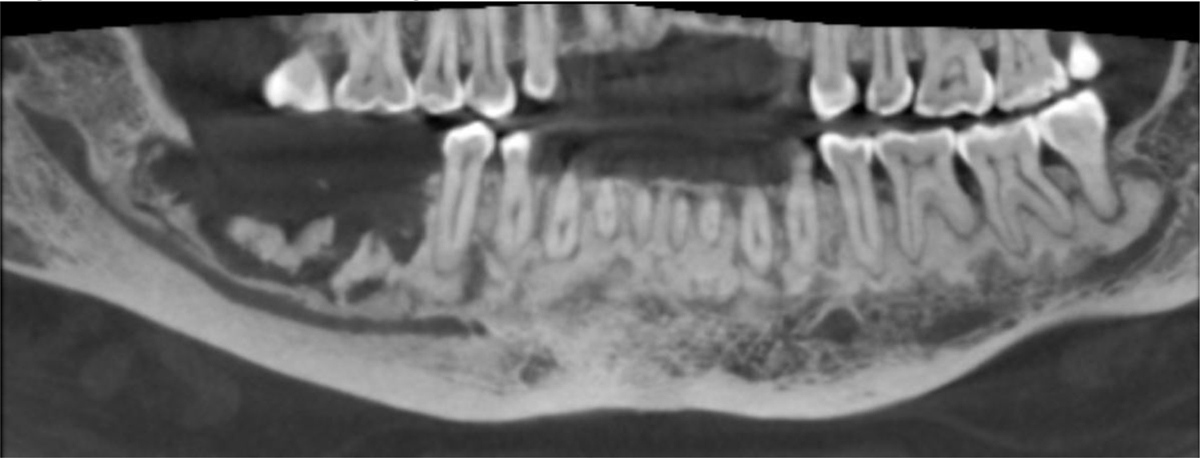

CBCT panoramic reconstruction illustrating bilateral mandibular involvement with mixed radiolucent and radiopaque areas, typical of florid COD.